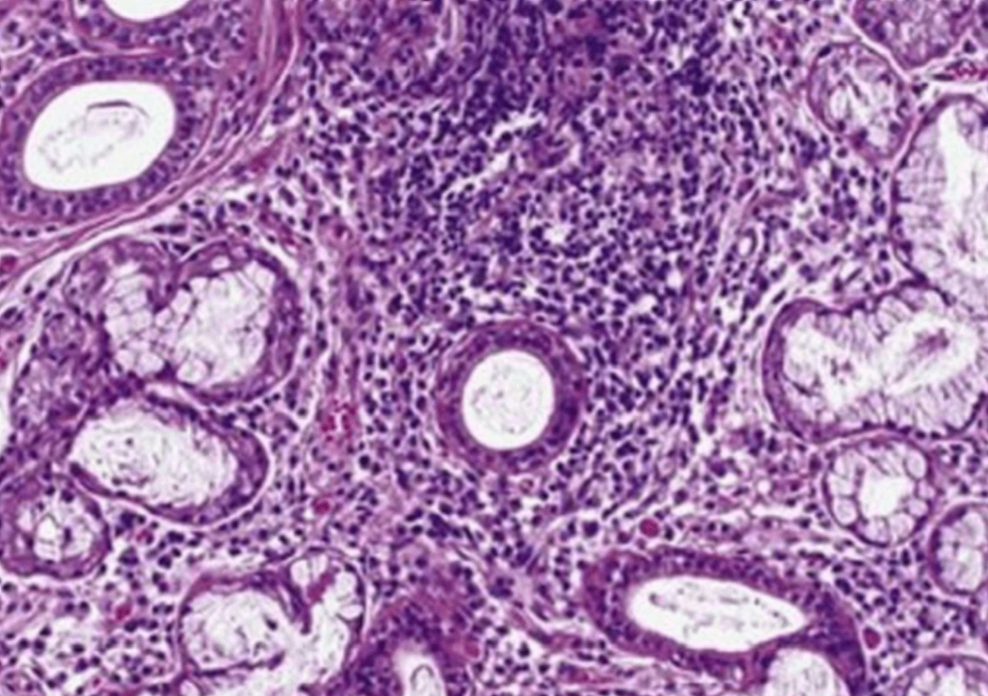

53세 여자가 1년 전부터 눈이 건조하고 입이 말라 음식을 삼키기 어렵다고 병원에 왔다. 침샘 조직검사 소견이다. 혈청에서 검출되는 자가항체는?

• 쇼그렌 증후근은 침샘, 눈물샘 등을 비롯한 외분비샘에 림프구가 침윤해 만성 염증을 초래하는 질환으로, 환자는 침과 눈물이 감소되어 건조증상을 호소한다. 이 외로는 소화액 분비량의 감소로 인한 위염, 관절염, 광과민성과 같은 피부 증상이 나타날 수 있다.

•쇼그렌 증후군을 확진하기 위해서는 혈액검사에서 Anti SS-A와 Anti SS-B 항체가 특이적으로 검출되어야 한다.